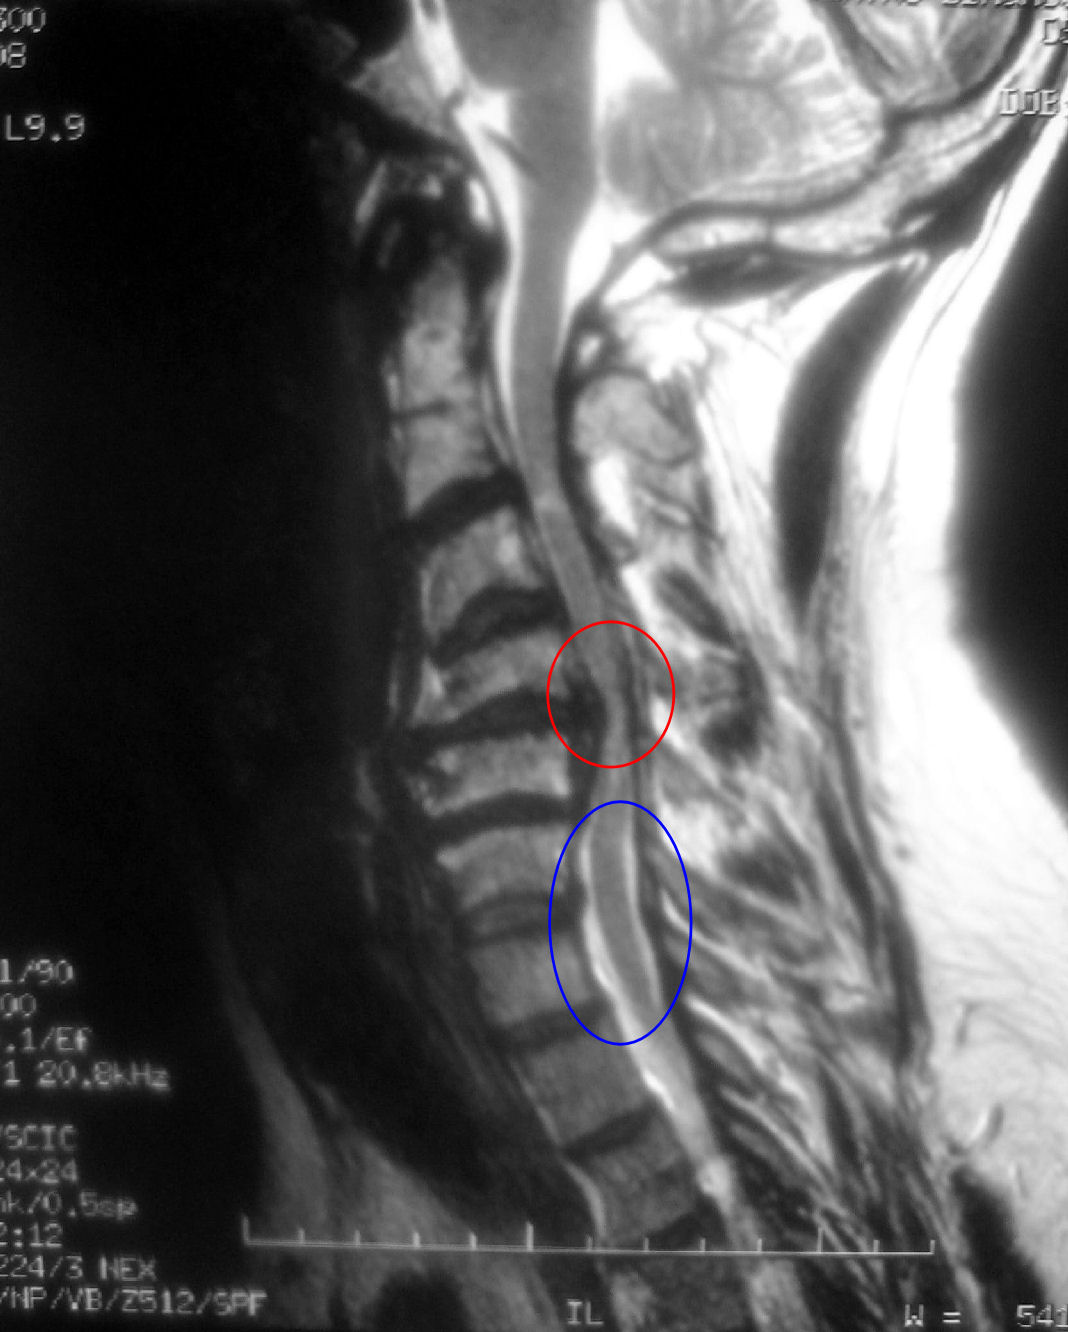

En esta imagen podemos ver la diferencia entre en segmento normal de la columna: En el interior del circulo azul donde la medula presenta un calibre normal (trazo gris vertical) y existe espacio entre esta y los huesos que la rodean (trazos blancos verticales a ambos lados del gris). En el interior del circulo rojo la medula ha disminuido de calibre y esta comprimida por las paredes de las vertebras que la rodean (han desaparecido los trazos blancos)

Por el interior del conducto que forman nuestras vertebras cervicales baja la medula espinal de la que salen los nervios que llevan a nuestros musculos las ordenes que manda el cerebro, y en sentido contrario la sensibilidad que recogen los nervios vuelve al cerebro recorriendo la medula. Cuando este conducto por el que baja la medula se estrecha comprime la medula impidiendo su adecuado aporte de sangre, de esta manera comienzan a destruirse las células nerviosas que son las responsables de llevar y traer la información del cerebro.